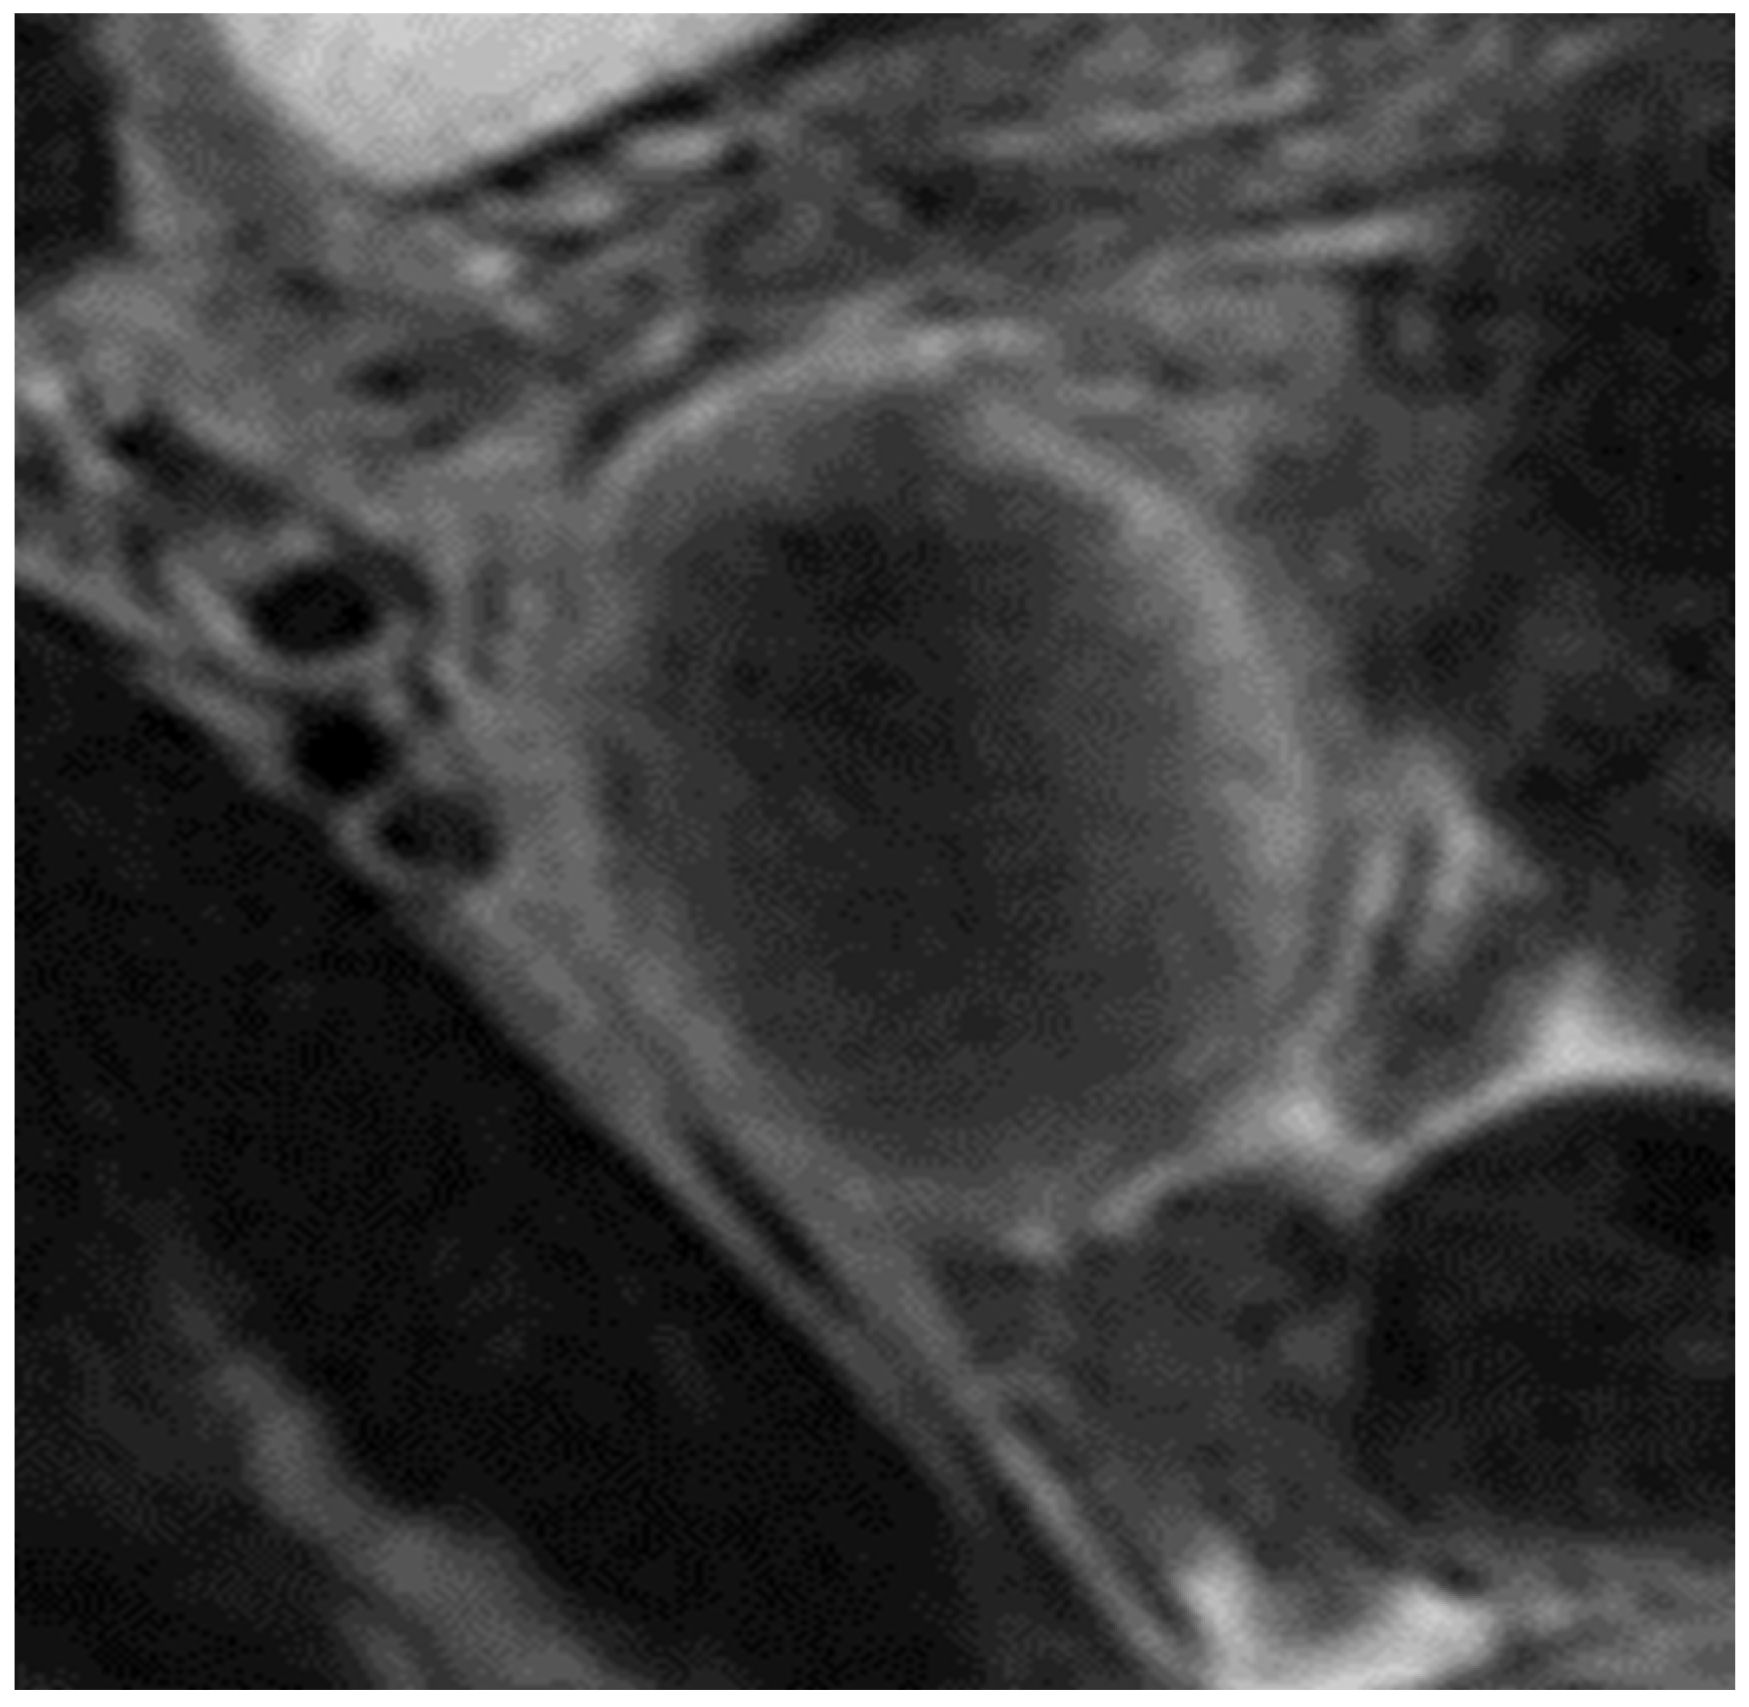

2. Case Presentation